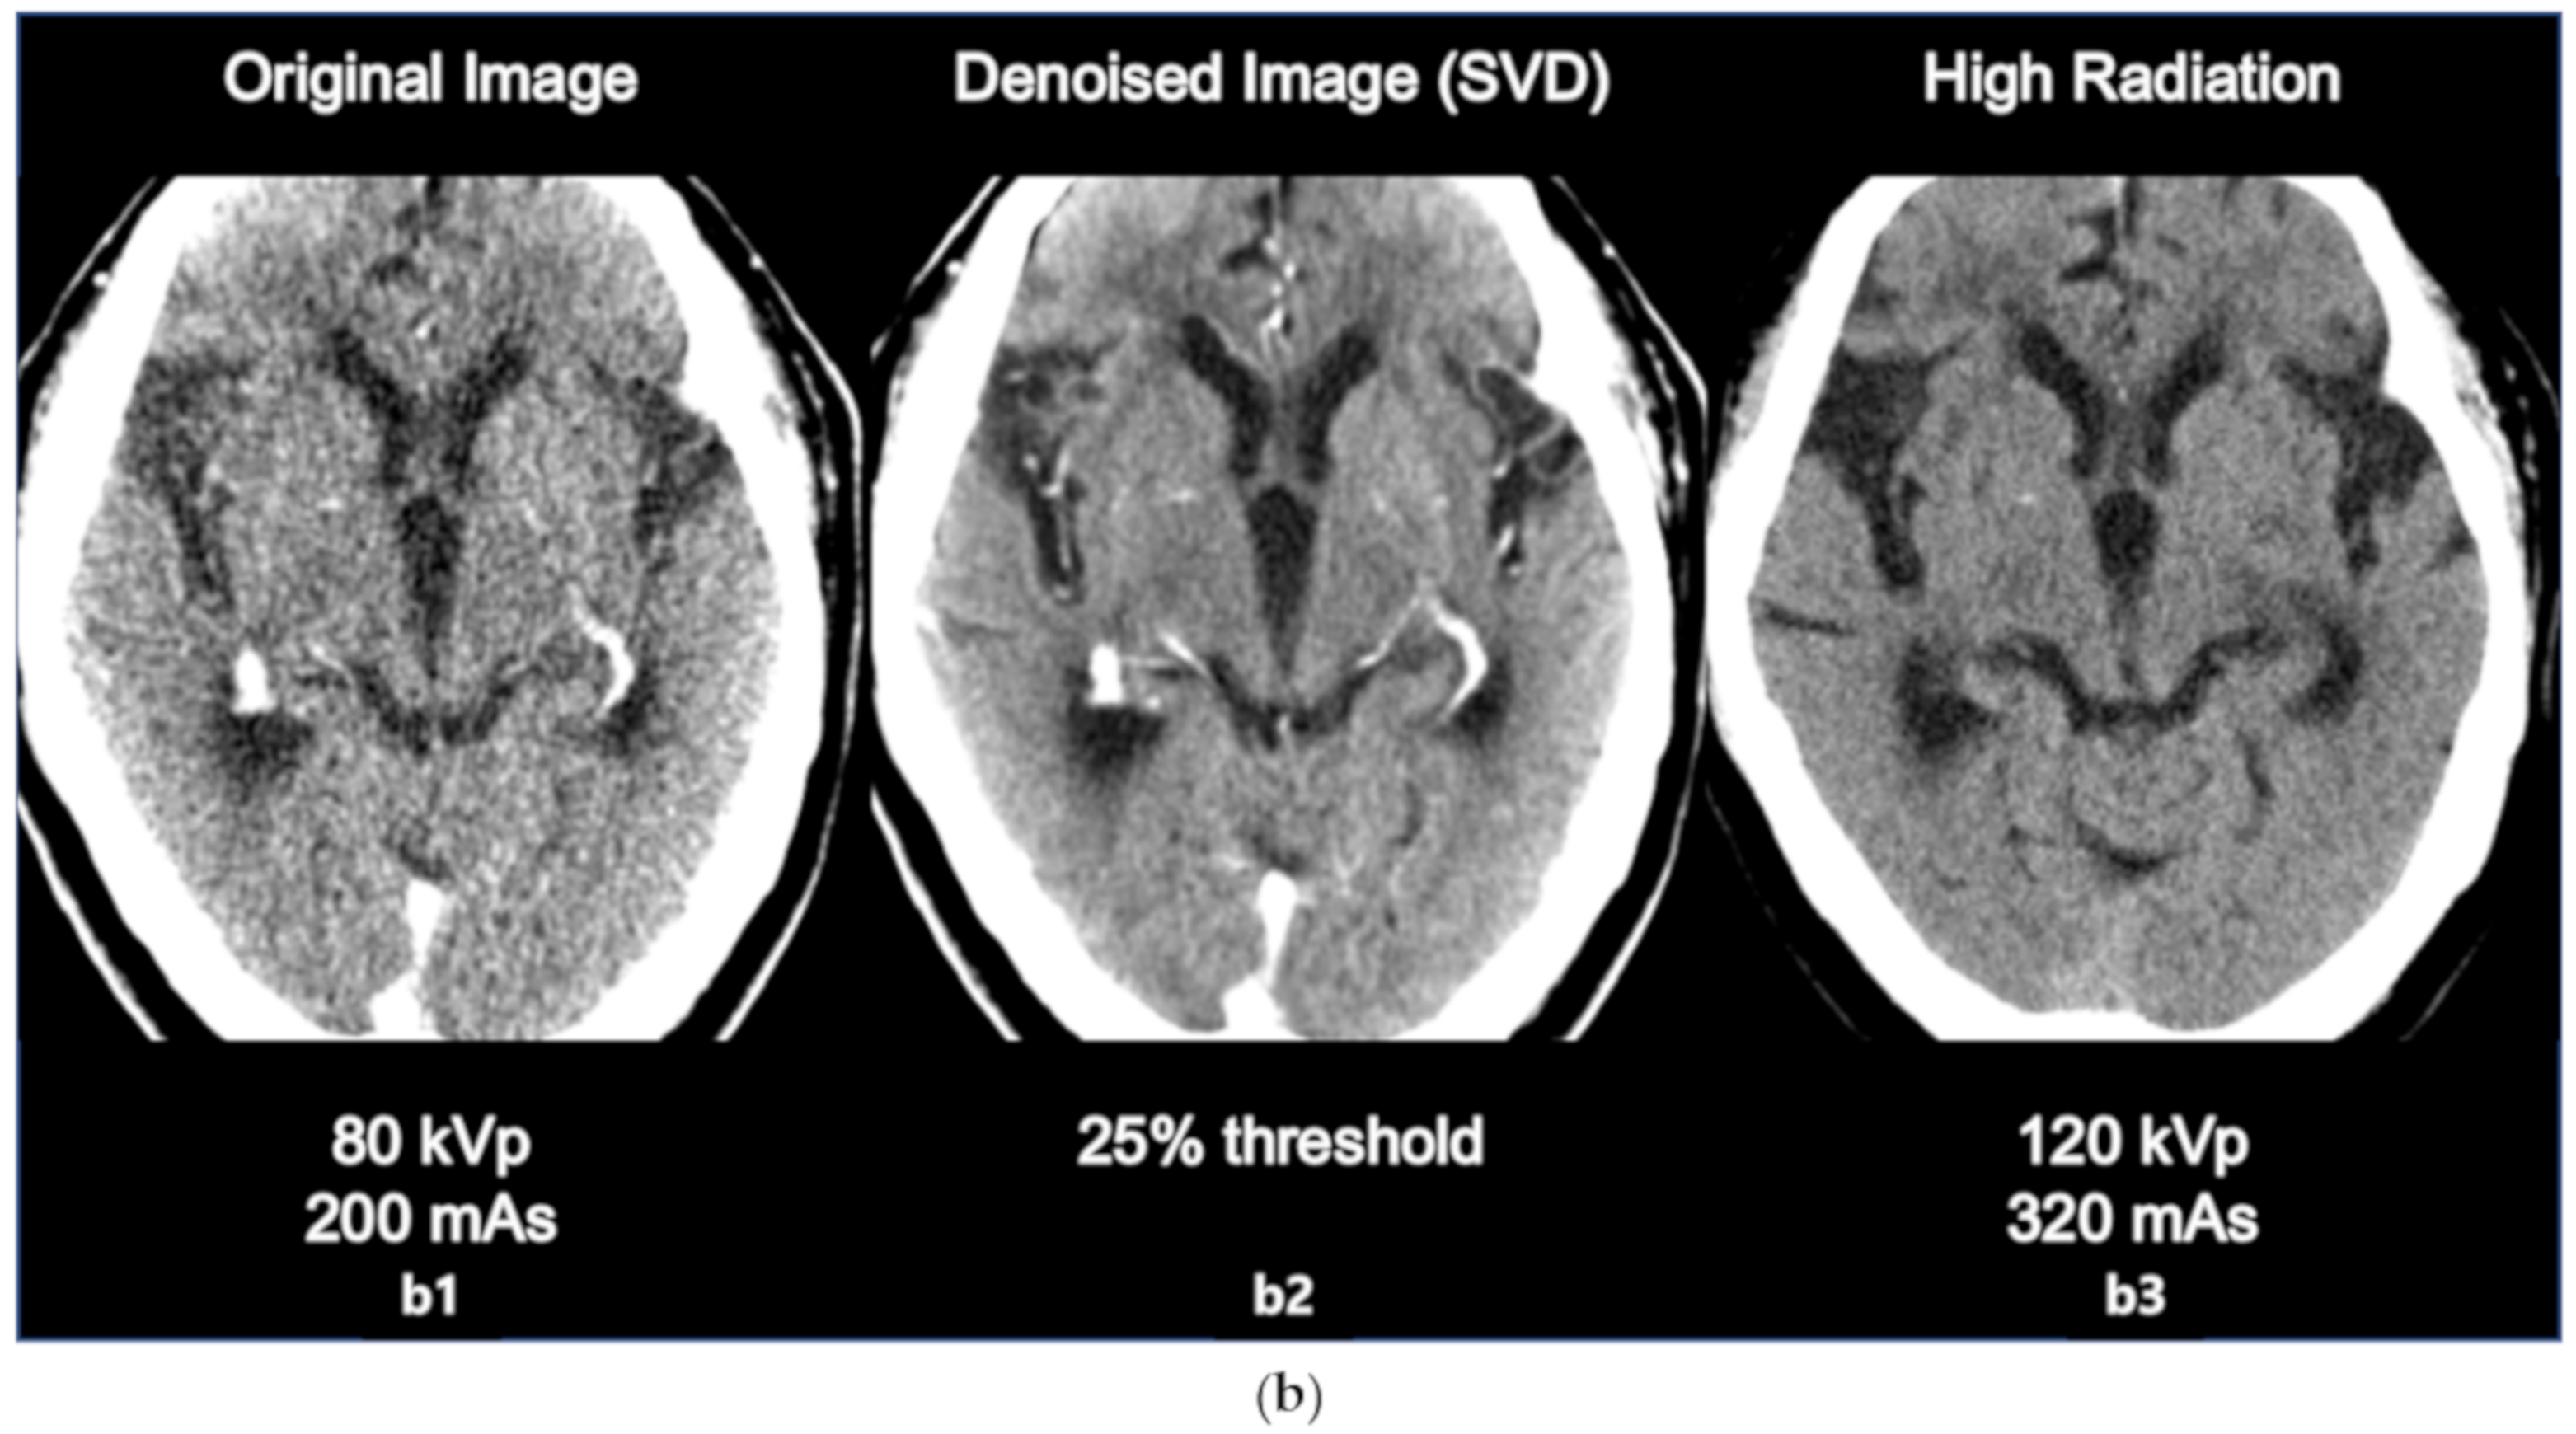

3.2. Comparison with High Radiation Dose Image